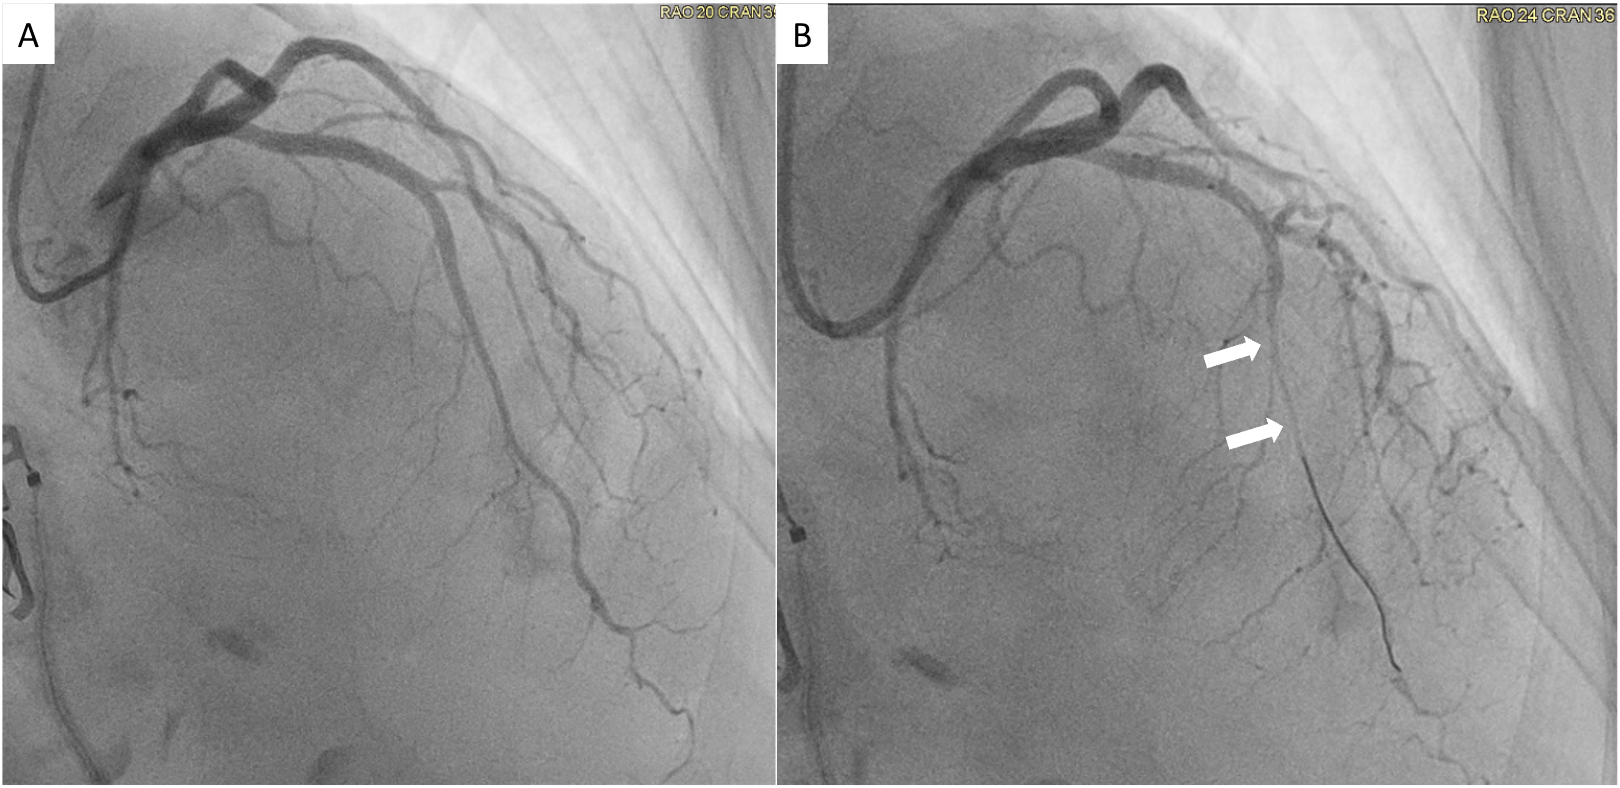

Diagnostic Techniques and Their Most Important Findings: Cardiac MRI performed using a 1.5T magnet revealed mild hypokinesis of the basal lateral wall, with corresponding focal elevation in native T1 and T2 times and transmural late gadolinium enhancement, associated with signs of microvascular obstruction (MVO). Findings were consistent with an acute myocardial infarction (Figure 1) of the basal lateral wall. Subsequent conventional coronary angiography confirmed the absence of obstructive coronary artery disease or coronary emboli. However, physiologic study demonstrated significantly reduced coronary flow reserve (CFR) at 1.6, suggesting microvascular disease. A provocative test with intracoronary acetylcholine demonstrated significant spasm of the left anterior descending coronary artery (Figure 2) accompanied by chest pain and ischemic ST changes on the ECG, confirming diagnosis of vasospastic angina.

Figure 1: Short axis oblique views of native T1 (A) and T2 (B) maps, post-contrast cine Steady-State Free Precession (C) and late gadolinium enhancement (D) of a 68-year-old female patient. Elevated native T1 and T2 times in the inferolateral wall (arrows in A and B, respectively) are demonstrated, as well as evidence of transmural infarction with signs of microvascular obstruction (arrows in C and D, asterisk in D).